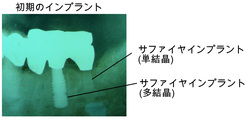

私のインプラント歴は古く、岡山でも早期に取り入れておりましたが、ただ単に部分的に歯がないからインプラントを埋入していたのです。